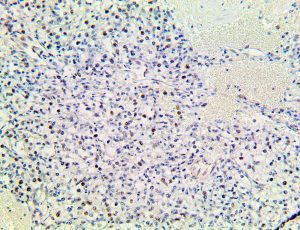

It is the ICU physician who is most likely to witness one of the deadliest manifestations of the abnormal immunological response, the cytokine storm syndrome (CSS). This response is also referred to by some as the cytokine release syndrome (CRS). CSS is characterized by continuous activation and expansion of macrophage and lymphocyte populations, which secrete large amounts of cytokines, causing the cytokine storm. This massive cytokine release is akin to hemophagocytic lymphohistiocytosis (HLH) disease, a syndrome characterized by initial unchecked and persistent activation of cytotoxic T lymphocytes and NK cells.

Clinical and laboratory manifestations of HLH include fever, enlarged liver and/or spleen, neurologic dysfunction, coagulopathy, liver dysfunction, cytopenias (i.e., low levels of erythrocytes, leukocytes, and/or platelets), hypertriglyceridemia, hyperferritinemia, hemophagocytosis, and eventually diminished NK cell activity as the immune system becomes progressively paralyzed. HLH can be familial (primary HLH) or secondary to another disease process (sHLH), such as rheumatic disease, in which it is referred to as macrophage activation syndrome (MAS, characterized by elevated ferritin).

This activation induces inflammatory monocytes to highly express IL-6, starting a localized and then systemic cascade effect that results in hyperproduction of IL-6, which accelerates the inflammatory process. Because IL-6 also increases vascular permeability, excessive levels cause blood vessels to become very leaky. This, along with clotting factors released from vascular endothelial cells, stimulates the coagulation cascade, resulting in microthrombosis (tiny clots), which leads to ischemia and tissue death of the kidney, intestines, heart, liver, brain and extremities.